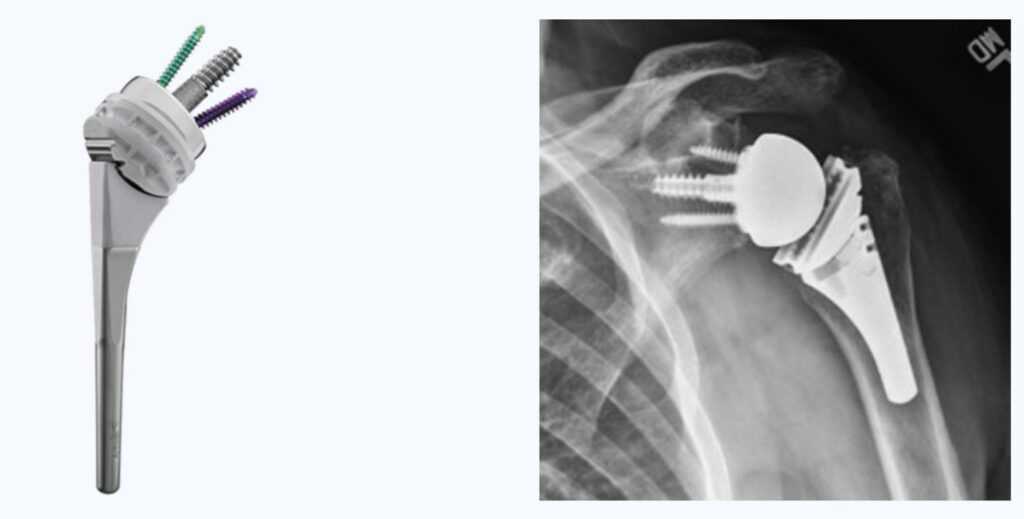

Abban az esetben, ha a tünetek konzervatív kezeléssel nem javulnak, a műtét jelenthet megoldás. A legtöbb esetben a legmegbízhatóbb megoldás az ún. reverz vállprotézis beültetése. Ezt a beavatkozást kombinált (altatás és regionális) érzéstelenítésben végezzük, a váll elülső részén ejtett bemetszéssel és körülbelül 1-1,5 órát vesz igénybe. A vállízületi felszíneket fémből és nagy szilárdságú műanyagból készült protézis komponensekkel cseréljük ki, a fájdalom megszüntetése és a mozgástartomány javítása érdekében. A reverz vállprotézis megakadályozza a felkarcsont elcsúszását a vállcsúcs irányába ezáltal visszaállítja az ízület stabilitását. Ez lehetővé teszi a deltoid izom és a megmaradt vállizmok hatékony működését és a funkció helyreállítását a fájdalomcsillapítás mellett.

A legtöbb esetben a betegek a protézis beültetés másnapján már hazamehetnek. A műtét után 4 hétig kartartó viselése javasolt, de a könyököt, a csuklót és a kezet alap tevékenységekhez használhatják. A sikerességi arány meghaladja a 90%-ot. A műtétet követően a mozgástartomány javulása általában jelentős, de ami legmegbízhatóbban javul az a fájdalom. A kockázatok közé tartozik a fertőzés (a pácienseimnél ez az arány kevesebb, mint 1%), valamint az alkatrészek időbeli meglazulása (az implantátumok 90%-a még 10 évvel a műtét után, 70-80%-a pedig 20 évvel a műtét után van is stabil).